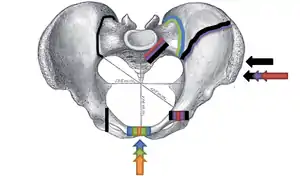

التصنيف

.png.webp)

كسور الحوض أكثر شيوعاً توصف بإستخدام واحد من نظامين تصنيفيين إثنين، مختلف الضغوط على الحوض تنتج مختلف الكسور، بعض الأحيان تحدد بالأعتماد على الاستقرار أو عدم الاستقرار.[6]

تصنيف (تايل) : نظام تصنيف تايل يعتمد على صلابة المركب العجزي الحرقفي الخلفي .

الاصابات من النوع أ، المركب الحرقفي العجزي سليم، حلقات الحوض فيها كسور مستقرة يمكن السيطرة عليها بدون تدخل جراحي .

الاصابات من نوع ب، بسبب إما قوة دورانية داخلية أو خارجية ينتج خراب جزئي في المركب العجزي الحرقفي الخلفي وعادة يكون غير مستقر .

الاصابات من النوع ج، تتضن خراب كلي للمركب العجزي الحرقفي الخلفي وعدم استقرار عامودي دوراني . هذه الإصابة تنتج من قوة عظيمة عادة من تصادم سيارات أو سقوط من ارتفاع أو ضغط شديد للمنطقة .

تصنبف (يونغ بورغيس) : نظام تصنيف يعتمد على آلية الإصابة : ضغط خلفي أمامي نوع 1، 2، 3 ، ضغط جانبي نوع 3,2,1 ، قص عامودي[3] أو مزيج من القوى . كسور الضغط الجانبي تتضمن كسور عرضية للعانة إما مماثل أو مقابل للأصابة الخلفية . الدرجة 1 : مصحوبة بضغط العجزي على جانبي التأثير الدرجة 2 : مصحوبة بكسر حرقفي خلفي ( هلالي ) على جانبي التأثير الدرجة 3 : مصحوبة بإصابة لأربطة الحرقفي العجزي الجانبية المقابلة

أكثر أنواع القوى شيوعاً، قوى الضغط الجانبية، من إصابات الحوادث المتحركة الجانبية وإصابات المشاة تنتج دوران داخلي .[7] عظم العانة العلوي والسفلي قد ينكسر أماميا، مثال الإصابات من القوة العامودية مثل السقوط من الاعلى، تؤدي إلى تلف الاربطة أو العظام . عند حدوث عدة قوى تدعى الإصابة الميكانيكية المركبة .

كسر (الكتاب المفتوح )

أحد الانواع الخاصة بكسر الحوض يسمى كسر ( الكتاب المفتوح ) ، عادة تنتج من تأثير ثقيل على المغبن (اصل الفخذ ) على جانبي العانة، مألوفة في إصابات حوادث الدراجات النارية، في هذا النوع من الاصابات، النصفيين الأيمن والايسر للحوض مفصولين عند الامام والخلف، الفتحة الامامية أكثر من الخلفية، مثل الكتاب المفتوح الذي يسقط على الارض ويقسم في الوسط، بالاعتماد على الشدة، ربما يتطلب عملية اعادة تصحيح جراحية قبل اعادة التأهيل.[8] القوى من الاتجاه الامامي أو الخلفي، مثل حوادث السيارات وجهاً لوجه، قد تسبب دوران خارجي لنصفي الحوض، اصابات الكتاب المفتوح . الكسور المفتوحة تزيد خطورة العدوى والنزيف من اصابات الاوعية الدموية تؤدي إلى ارتفاع معدل الوفيات.[9]